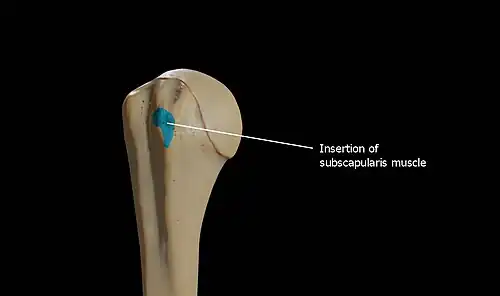

Lesser tubercle

The lesser tubercle (tuberculum minus; lesser tuberosity) is smaller, anterolaterally placed to the head of the humerus. The lesser tubercle provides insertion to subscapularis muscle. Both these tubercles are found in the proximal part of the shaft. The crest of the lesser tubercle forms the medial lip of the bicipital groove and is the site for insertion of teres major and latissimus dorsi muscles.

The lesser tuberosity, is more prominent than the greater: it is situated in front, and is directed medialward and forward. Above and in front it presents an impression for the insertion of the tendon of the subscapularis muscle.[2]

The infraspinatus and teres minor insert on the greater tubercle, and work to laterally, or externally, rotate the humerus. In contrast, the subscapularis muscle inserts onto the lesser tubercle and works to medially, or internally, rotate the humerus.